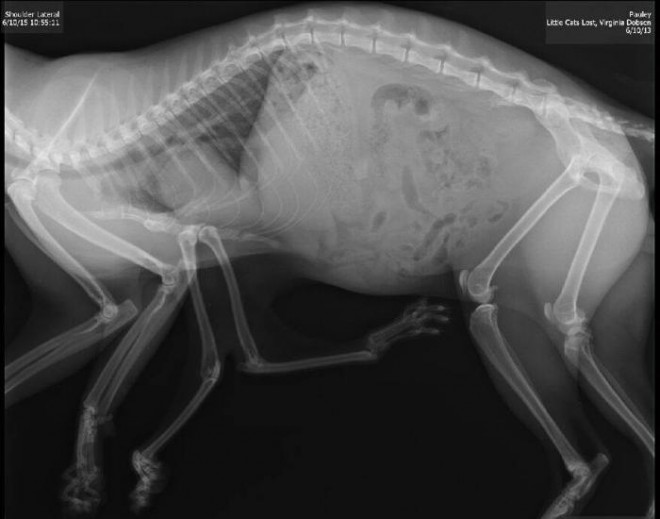

Pauly vive a Edmonton in Canada e ha sei zampe… non ci potete credere!?

In effetti, si tratta di una patologia rarissima che colpisce un gatto su 10mila. È stato trovato lo scorso aprile nella parte sud-ovest della città da alcuni cittadini che lo hanno aiutato e hanno contattato l’associazione animalista Little Cats Lost che lo ha subito accolto.

Secondo i medici la malformazione di Pauly dipende probabilmente dal fatto che dentro l’utero della madre ci fossero due gattini e che uno abbia inglobato l’altro.

Data la grande difficoltà nella deambulazione, un intervento chirurgico è ormai necessario per il gatto che ha già sette anni e presenta una grave displasia dell’anca.